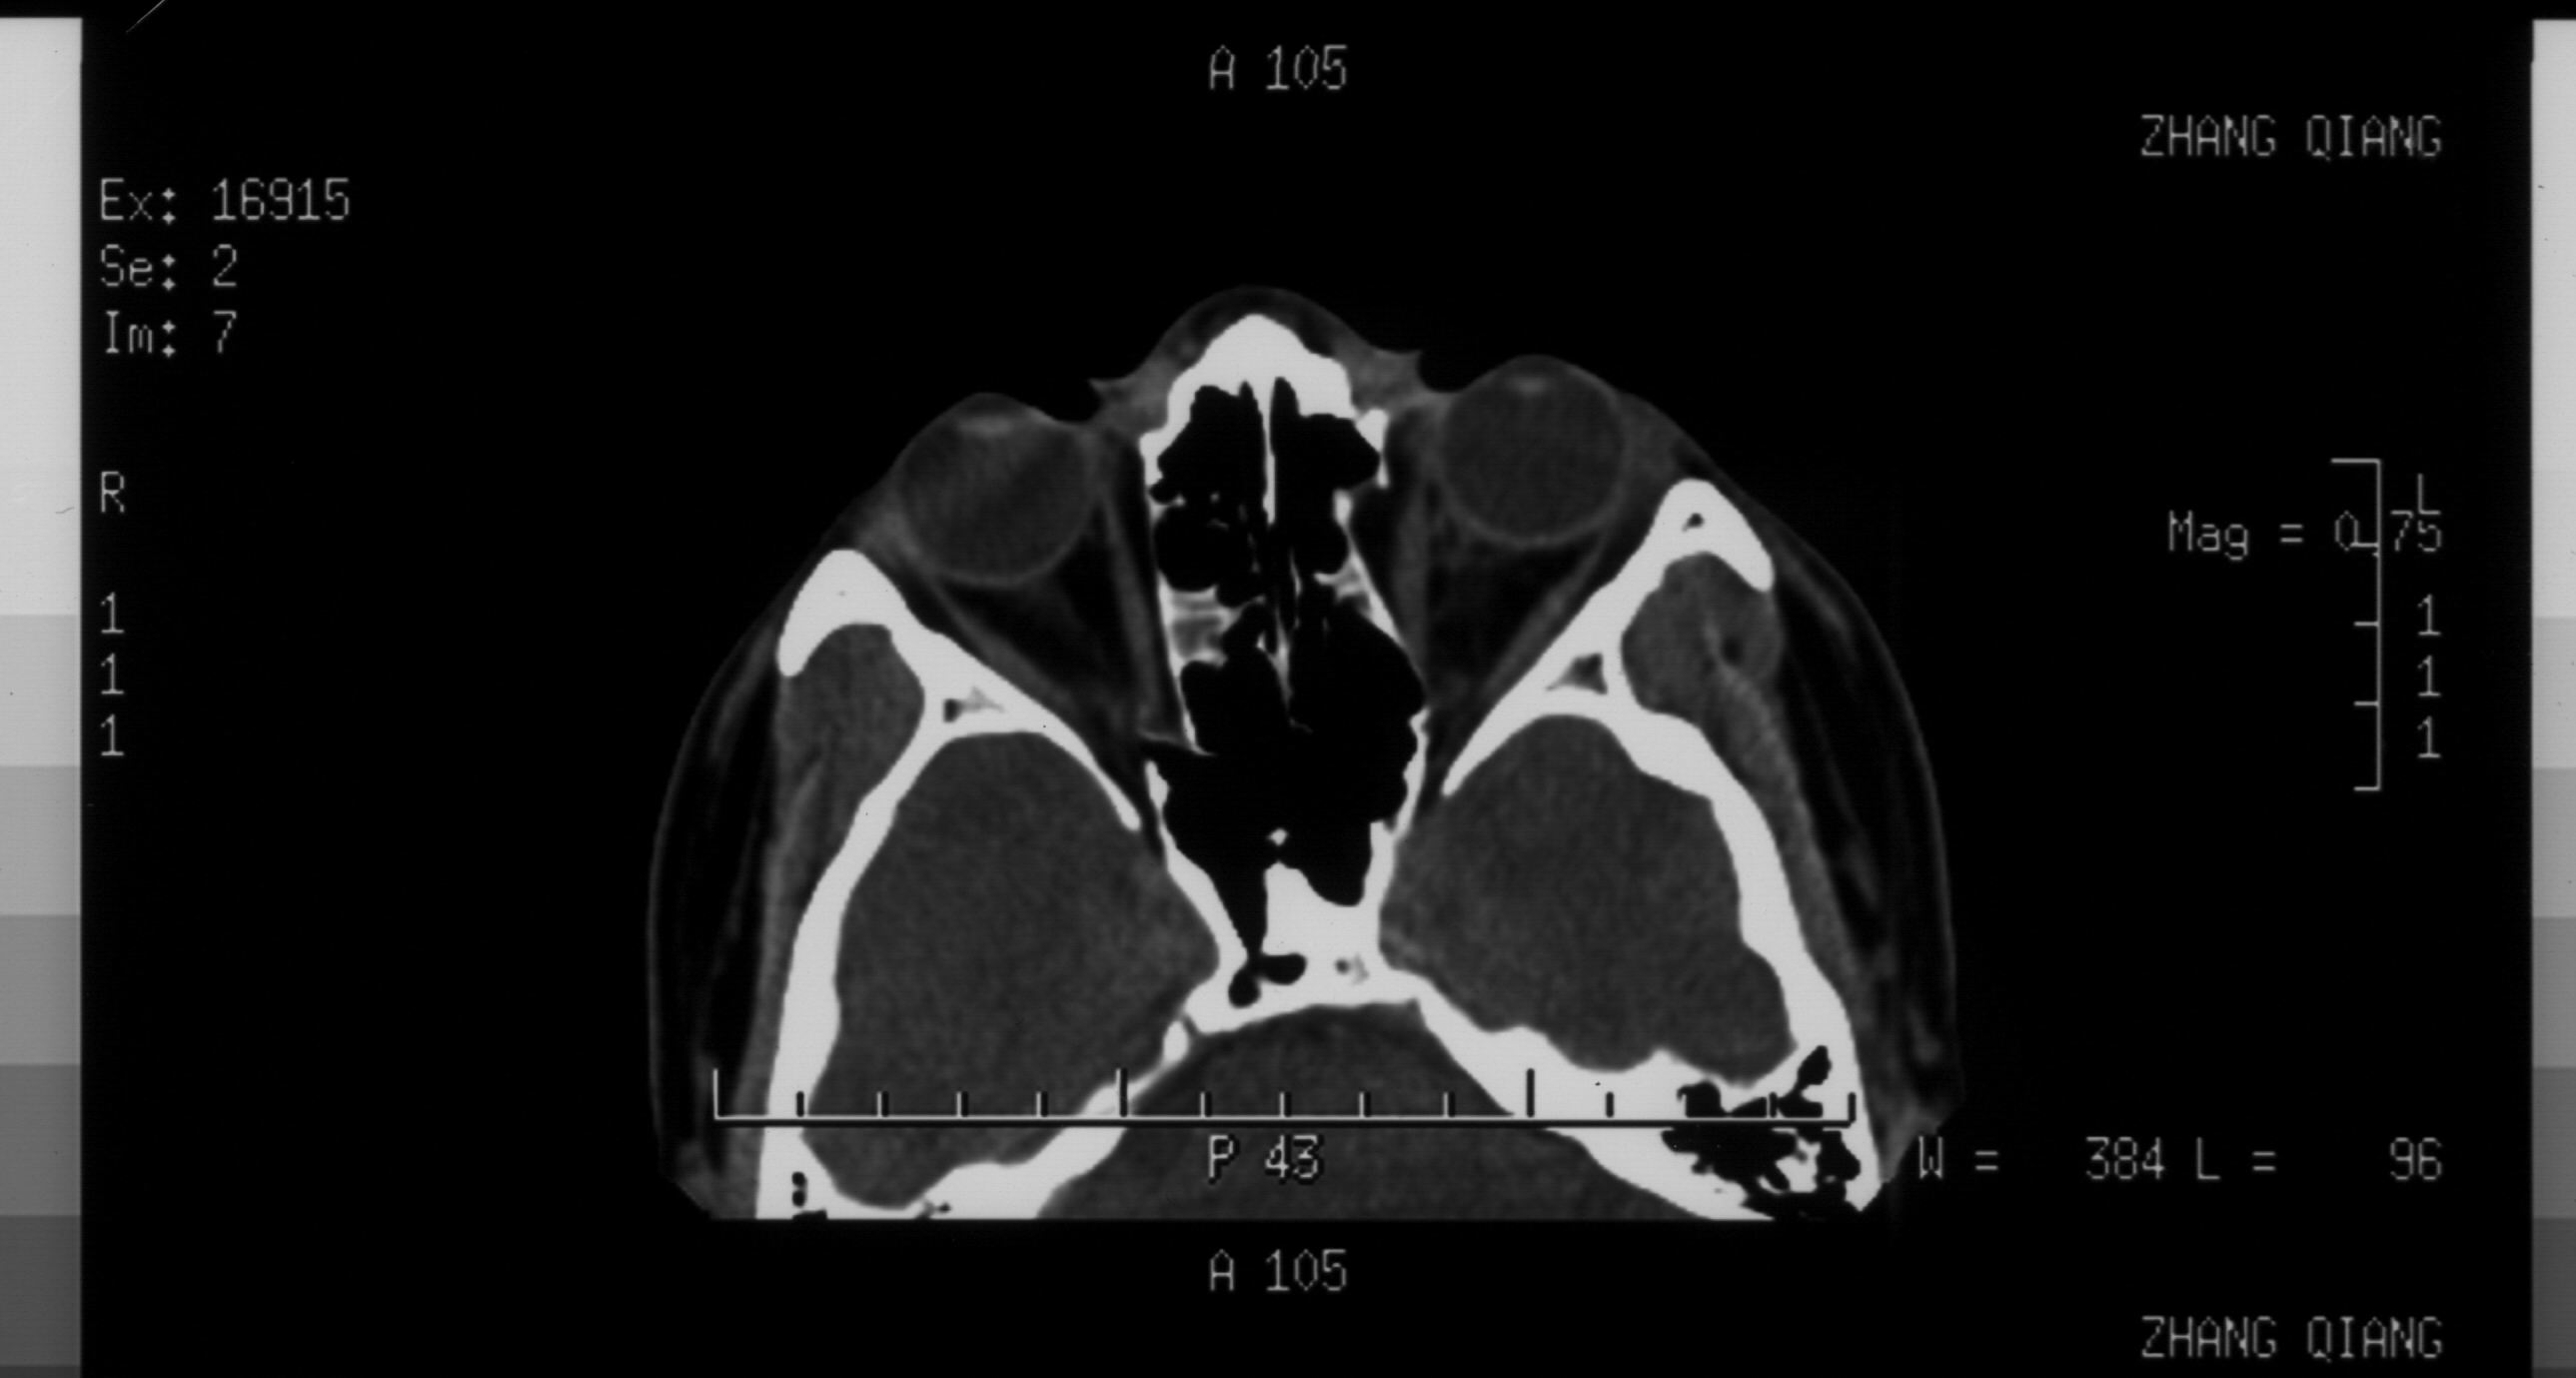

双眼拳击伤 双眼全方位复视

请解读一下ct片

你的CT片分析结果,至少有两点是可以确定的。1、双侧眼眶内侧鼻多发骨折 2、鼻骨骨折。

图560:箭头所示左侧鼻骨及鼻中隔骨折明确。另外,对于眼科医生应同时关注鼻泪管。通常这个部位容易被放射科大夫所忽视。